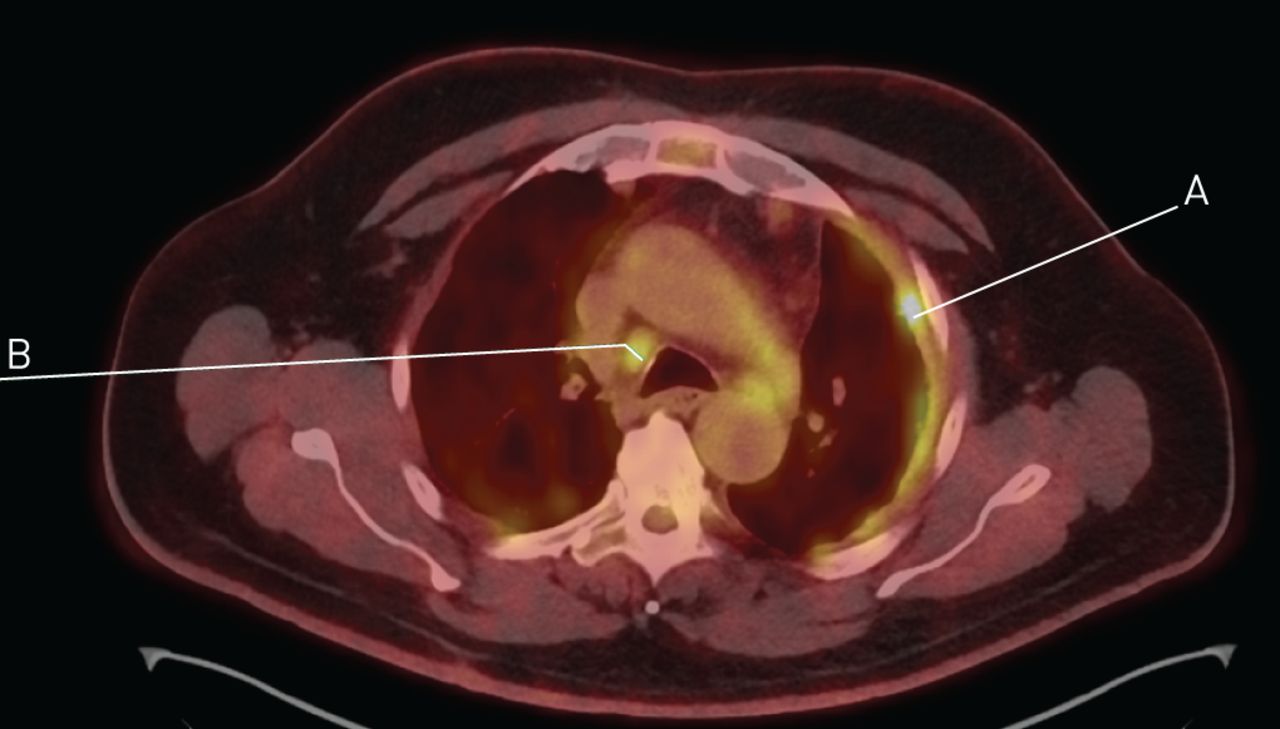

It most commonly occurs in the linings of the lungs or the abdomen. Malignant pleural mesothelioma is the most common type of mesothelioma cancer and is almost always caused by the inhalation of asbestos fibers. Mesothelioma is a relatively rare terminal cancer caused by asbestos exposure.

Pleural mesothelioma causes the only known pleural mesothelioma cause is asbestos exposure. Am j respir crit care med vol. Pleural effusion is a common symptom of malignant pleural mesothelioma.

Mesothelioma treatments are available, but for many people with mesothelioma, a cure isn't possible. Mesothelioma of the pleura, which affects the tissue around the lungs, causes symptoms and symptoms such as: While a pleural effusion may be a symptom of pleural mesothelioma itself, the condition can also cause its own symptoms.